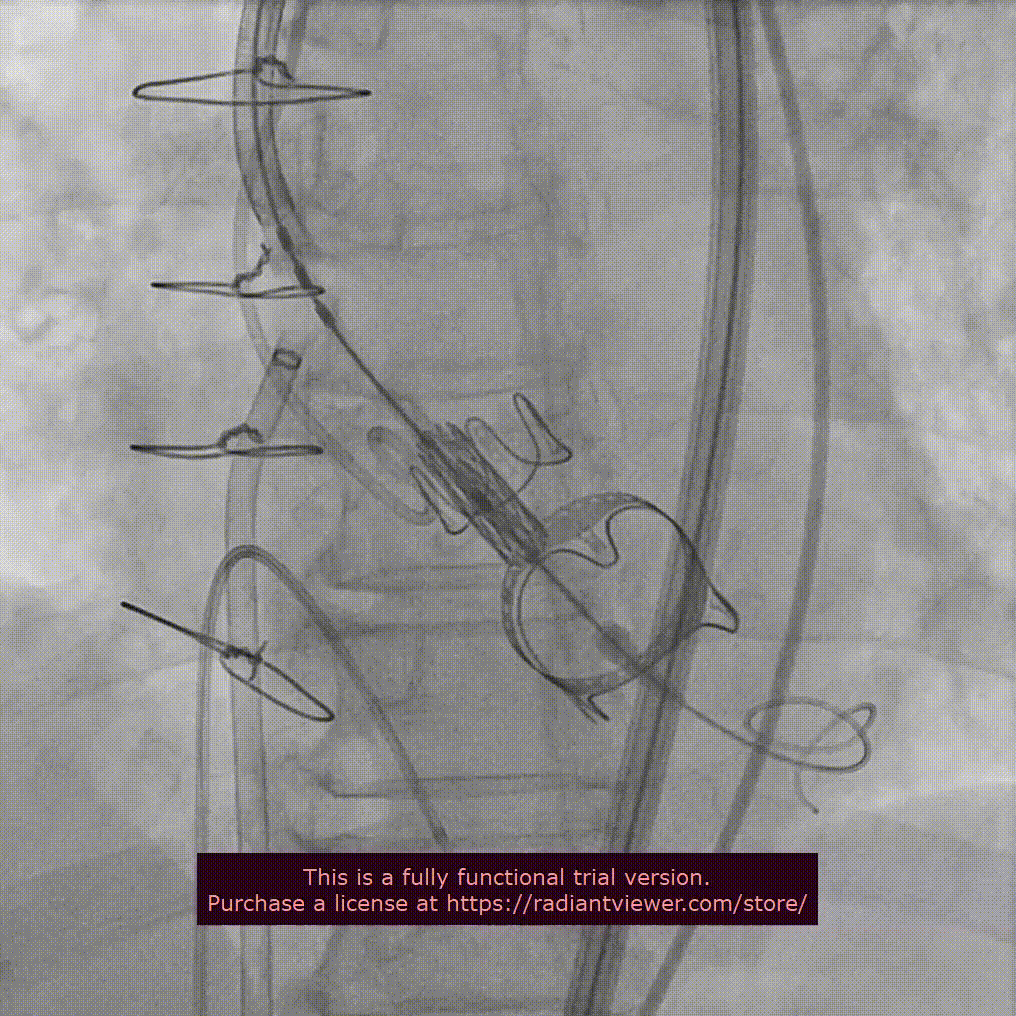

近日,中国医学科学院阜外医院潘湘斌教授团队,在多科室的通力配合下,凭借扎实的手术功底顺利完成一例经导管主动脉瓣和二尖瓣瓣中瓣置换术。

手术过程